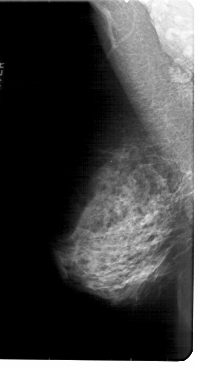

A_1819_1.LEFT_MLO

LEFT_CC LINES 5281 PIXELS_PER_LINE 2881 BITS_PER_PIXEL 12 RESOLUTION 43.5 NON_OVERLAY

LEFT_MLO LINES 5491 PIXELS_PER_LINE 2956 BITS_PER_PIXEL 12 RESOLUTION 43.5 NON_OVERLAY